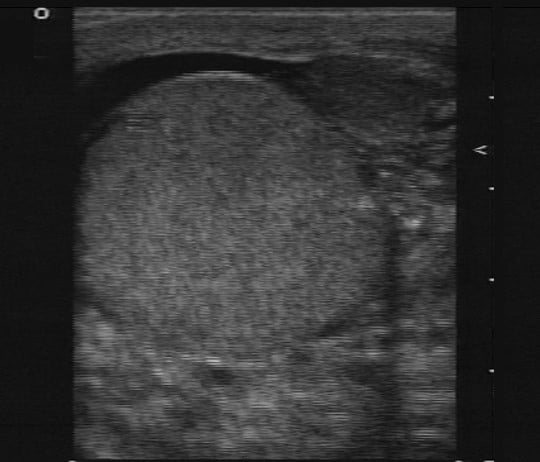

7. Finally, add power Doppler to compare the pattern of flow in both testicles. Decreased flow in the affected size is suggestive of testicular torsion, while an increase in blood flow is more common in inflammatory condition as epididymitis or orchitis (Figure 3).

Figure 3. Testicular ultrasound with absence of blood flow. Courtesy of Michael Blaivas, MD